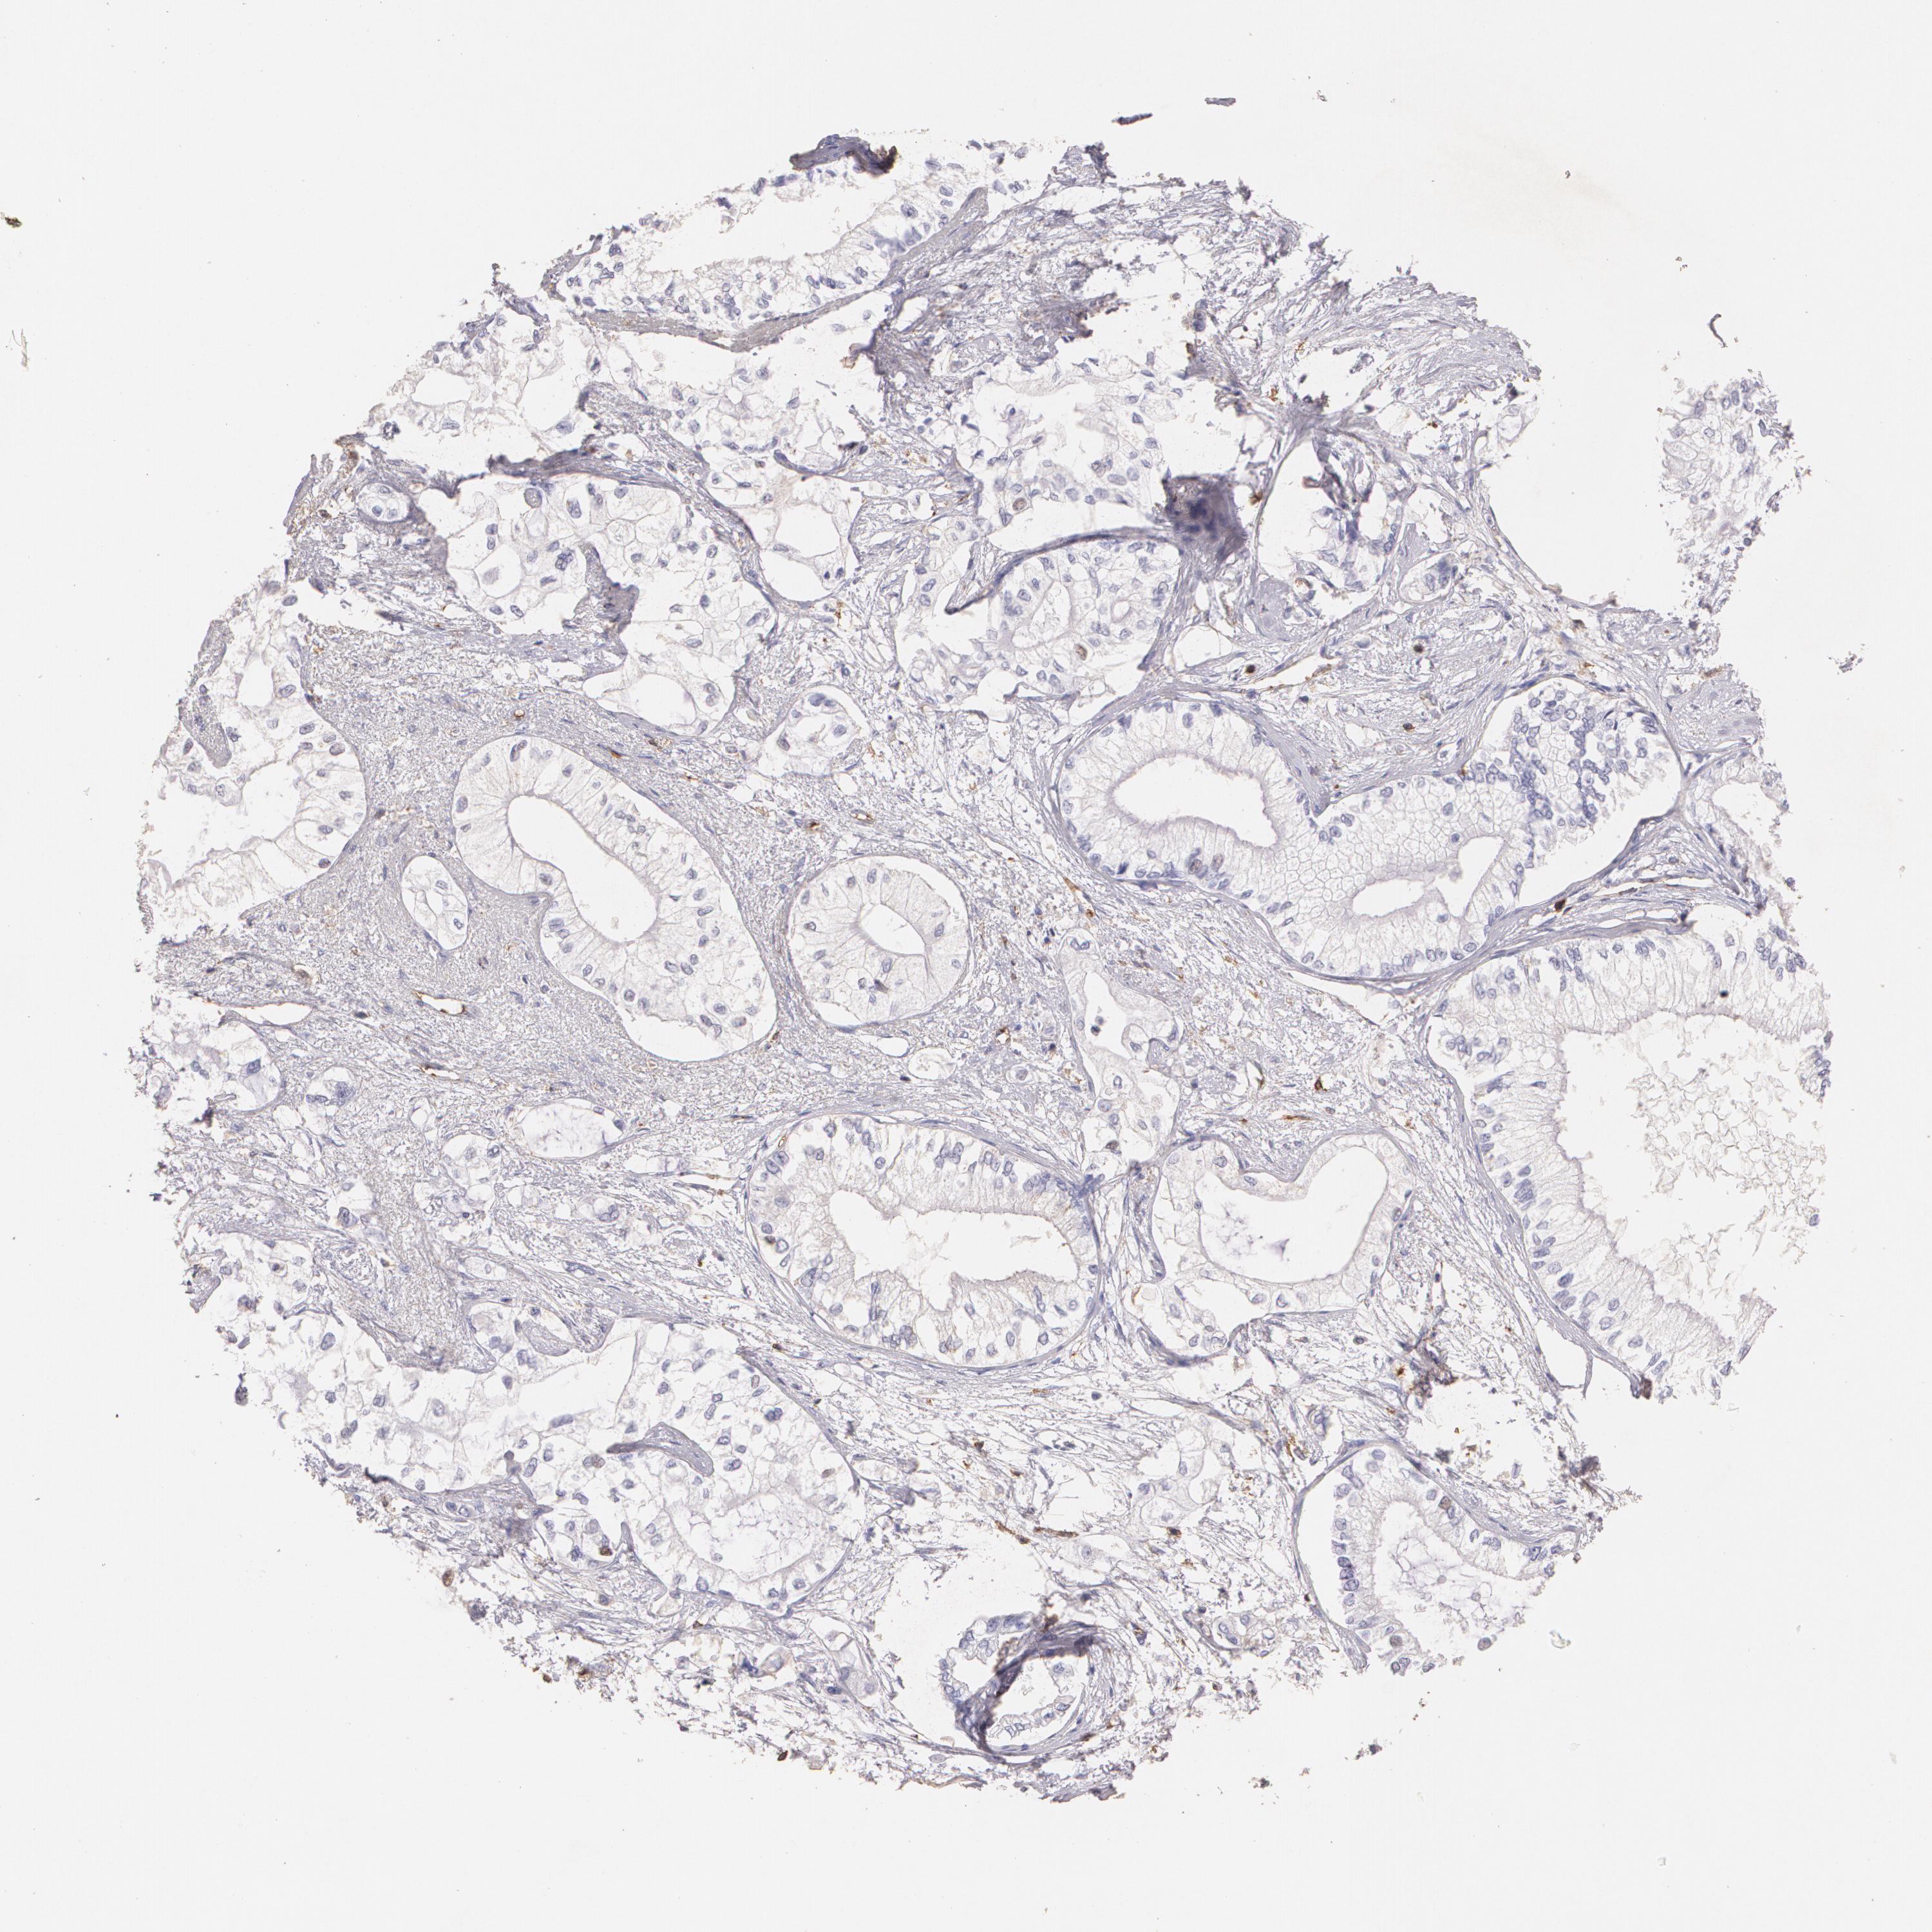

PANCREATIC CANCER - Protein expressioni

A mouse-over function shows sample information and annotation data. Click on an image to view it in a full screen mode. Samples can be filtered based on level of antibody staining by selecting one or several of the following categories: high, medium, low and not detected. The assay and annotation is described here.

Note that samples used for immunohistochemistry by the Human Protein Atlas do not correspond to samples in the TCGA dataset.

Antibody stainingi

Antibody staining in the annotated cell types in the current human tissue is reported as not detected, low, medium, or high, based on conventional immunohistochemistry profiling in selected tissues. This score is based on the combination of the staining intensity and fraction of stained cells.

Each image is clickable and will lead to virtual microscopy that enables deeper exploration of all samples and also displays staining intensity scores, fraction scores and subcellular localization as well as patient and tissue information for each sample.

Antibody CAB002441

Antibody CAB031481

Staining

High

Medium

Low

Not detected

Intensity

Strong

Moderate

Weak

Negative

Quantity

>75%

75%-25%

<25%

None

Location

Nuclear

Cytoplasmic/membranous

Cytoplasmic/membranous,nuclear

Adenocarcinoma, NOS

Adenocarcinoma, metastatic, NOS